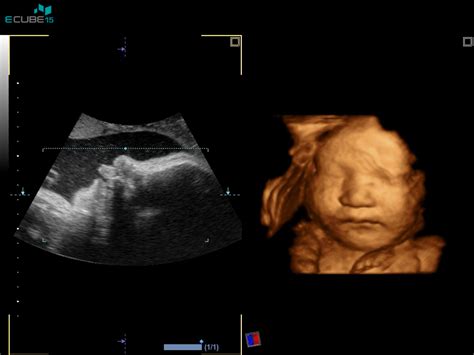

Prvi ultrazvočni pregled, ne glede na način zanositve, je pomemben mejnik. Njegov namen je potrditev nosečnosti, ocena velikosti in oblike gestacijske vrečke ter rumenjaka, ter prisotnost in velikost ploda. Ženske po OBMP postopku imajo prvi pregled običajno med 7. in 8. tednom, spontano zanositve pa med 9. in 10. tednom. V zgodnji nosečnosti lahko odstopanja v datumu oploditve ali ugnezditve povzročijo zelo različne slike na ultrazvoku.

Po 12. tednu nosečnosti se začne meriti dolžina ploda od glave do trtice (CRL), kar je najbolj natančno merilo gestacijske starosti. Med 20. in 22. tednom se opravi morfološki ultrazvočni pregled, ki omogoča zgodnjo oceno razvoja ploda.